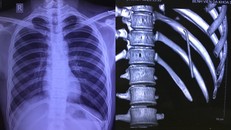

Hình ảnh chiếc đinh trong khoang phổi nam bệnh nhân. (Ảnh: BVCC)

(Ngày Nay) - Chiếc đinh tự di chuyển từ vai xuống khoang màng phổi khiến nam thanh niên đau nhiều vùng đáy phổi trái, khó thở, phải nhập viện.

Hình ảnh gỡ chiếc đinh khổng lồ ra khỏi nhu mô phổi - Ảnh: VTC News

(Ngày Nay) - Chiếc đinh cố định xương đòn bị gãy của người đàn ông đã tự di chuyển qua đỉnh phổi, đâm xuyên qua tủy sống.